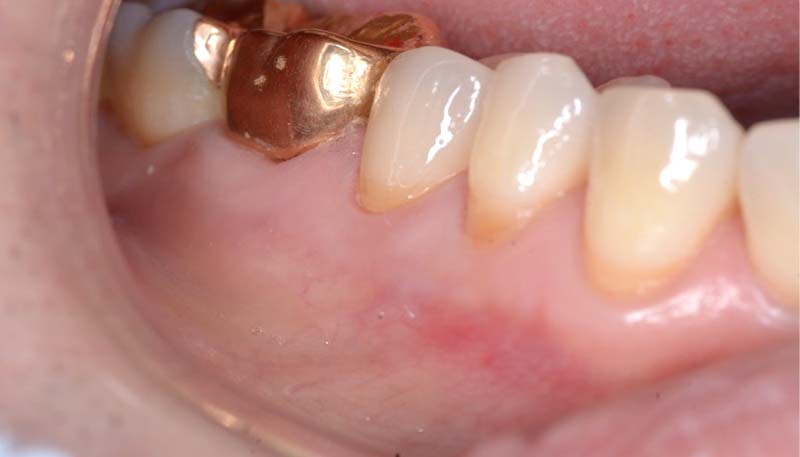

Case.03

インプラントの症例 インプラントの症例

治療前〜治療後のレントゲン写真

患者様の要望過去に治療したブリッジを外し咬み合わせの平面を整えて、被せ物や詰め物を綺麗にしたい。

治療期間10ヶ月

治療費用約1,600,000円

治療内容インプラント2本、アンカースクリューを用いた部分矯正、

セラミックによる補綴治療

治療のリスクセラミックの破折の

可能性